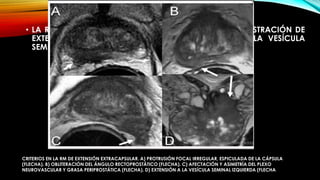

• LA RM HA DEMOSTRADO SER MÁS PRECISA EN LA DEMOSTRACIÓN DE

EXTENSIÓN EXTRACAPSULAR Y LA PARTICIPACIÓN DE LA VESÍCULA

SEMINAL Y TAMBIÉN PUEDE EVALUAR LINFADENOPATÍA

CRITERIOS EN LA RM DE EXTENSIÓN EXTRACAPSULAR. A) PROTRUSIÓN FOCAL IRREGULAR, ESPICULADA DE LA CÁPSULA

(FLECHA). B) OBLITERACIÓN DEL ÁNGULO RECTOPROSTÁTICO (FLECHA). C) AFECTACIÓN Y ASIMETRÍA DEL PLEXO

NEUROVASCULAR Y GRASA PERIPROSTÁTICA (FLECHA). D) EXTENSIÓN A LA VESÍCULA SEMINAL IZQUIERDA (FLECHA